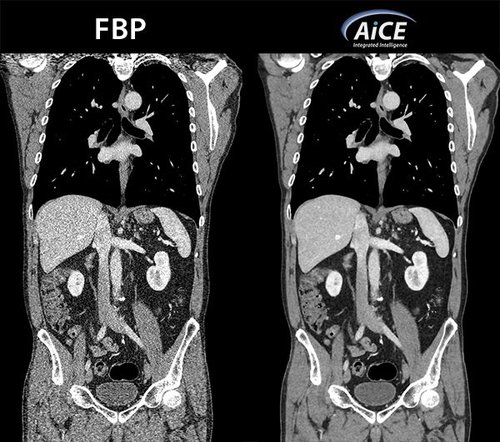

Mit AiCE, kurz für Advanced intelligent Clear-IQ Engine, kann der Aquilion One PRISM Edition besonders scharfe, klare und präzise Bilder in kürzester Zeit gewinnen. Die KI unterstützt die Reduktion von Bildrauschen auf ein Minimum und ermöglicht klare Aufnahmen mit sehr gut erkennbaren Strukturen auch bei niedrigem Kontrast. Gleichzeitig bringt sie eine automatische Anpassung des Kontrasts mit sich. Weiterhin ermöglicht sie eine schnelle kV-Umschaltung und eine patientenspezifische mA-Modulation, die wiederum mit einer Deep Learning-Rekonstruktion kombiniert wird, um eine hervorragende Energietrennung zu erzielen und Bildrauschen weiter zu reduzieren.